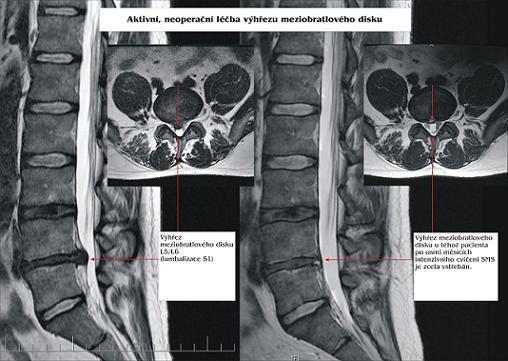

Radi by sme Vás, ktorých trápia bolesti chrbtice, či kĺbov, povzbudili reálnym príkladom jednej našej klientky.

Snímok nižšie je dôkazom toho, ako SM systém môže pomôcť už po 4 mesiacoch cvičenia.

V lekárskej správe bola diagnóza "rozsiahla dorzálna extrúzia s presahom 9 mm".

Najnovšia lekárska správa hovorí o plošnej protrúzii disku s presahom 5mm.

4 mesiace cvičila pravidelne a potom sporadicky.

Začala cvičiť v januári tohto roku a keby vydržala cvičiť pravidelne každý deň, je veľmi pravdepodobné, že by extrúzia bola úplne vyliečená.

Prvé snímky sú z 22.4.2015

Druhé zo 4.7.2016

Priatelia, nezúfajte, aj v takýchto prípadoch, kde už je indikácia na operáciu, sa dá stav zlepšiť, treba len vytrvalosť a pravidelné cvičenie. Zo začiatku pod odborným dohľadom, neskôr len sám doma.